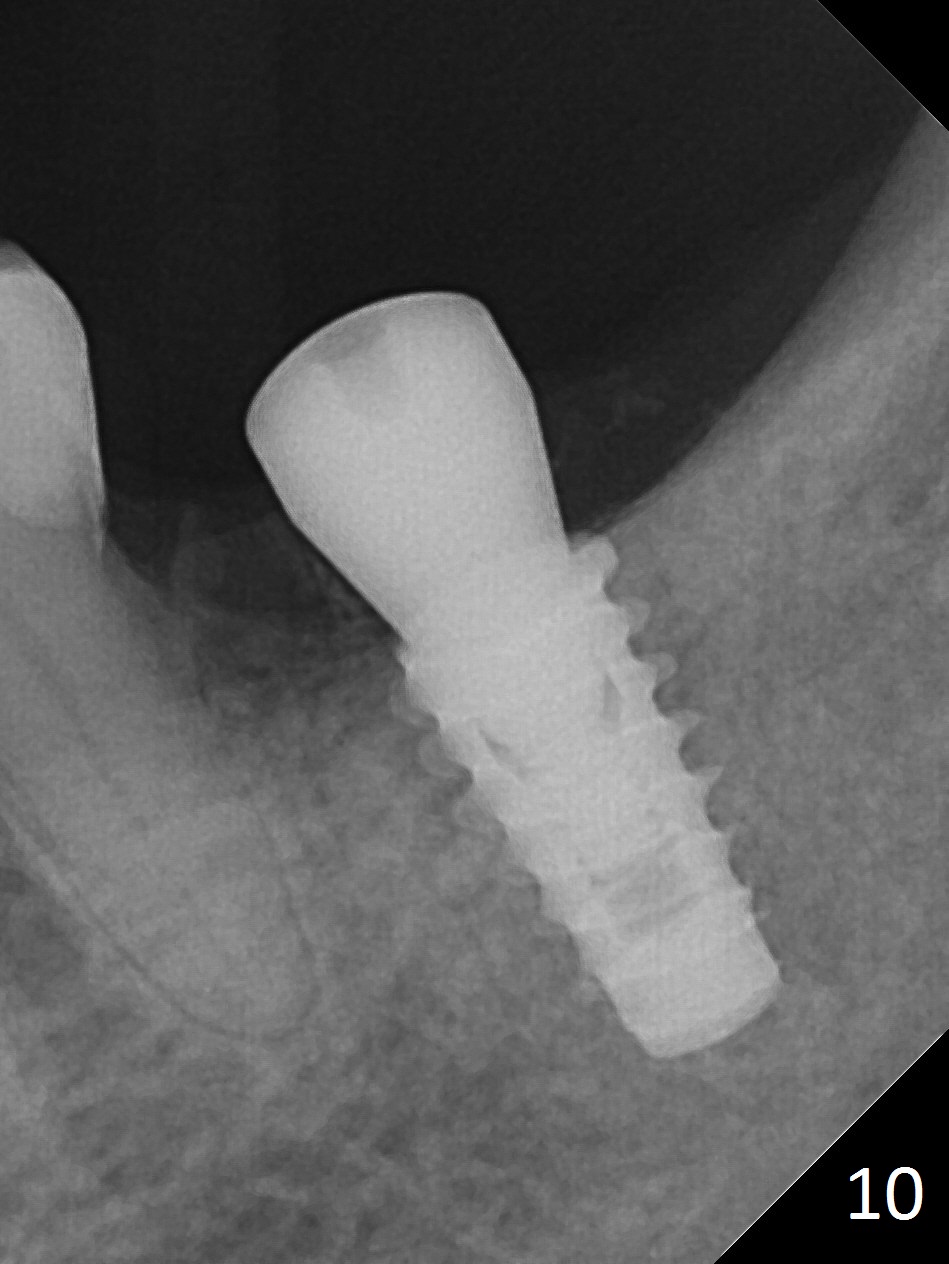

There is no apparent bone loss 4 months postop (Fig.10).  There is chewing pain in spite of occlusal adjustment 7 months post cementation (Fig.11-13: increased radiolucency around the implant).  The crown/abutment is removed and a healing abutment is placed (6x3 mm); the implant is stable.  The patient return for re-evaluation in 3 months (15 months postop); radiolucency appears to reduce (Fig.14).  But there is pain when the healing abutment is being removed.  After local anesthesia, the implant is removed with a wrench.  Following debridement of the osteototomy (intact, although tender), a 5x10 mm dummy implant with SLA surface is placed (Fig.15).  After 5.5 mm tap, a 5.5x8.5 mm implant is placed with >50 Ncm (Fig.16).  A 6.8x5 mm healing abutment is placed, followed by periodontal dressing.  Re-analysis of preop CBCT shows that the bone density at the site is low: 70 units average.  Progressive loading is necessary for this case 4-6 months postop.  The soft and hard tissues around the implant seem to heal 4 months postop (Fig.17).